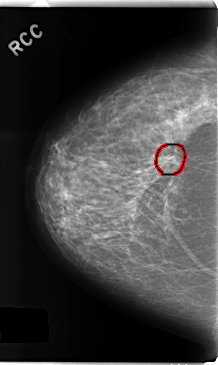

C_0242_1.RIGHT_CC

RIGHT_CC LINES 4736 PIXELS_PER_LINE 2824 BITS_PER_PIXEL 12 RESOLUTION 50 OVERLAY

FILE: C_0242_1.RIGHT_CC.OVERLAY

TOTAL_ABNORMALITIES 1

ABNORMALITY 1

LESION_TYPE CALCIFICATION TYPE PLEOMORPHIC DISTRIBUTION CLUSTERED

LESION_TYPE MASS SHAPE ARCHITECTURAL_DISTORTION MARGINS SPICULATED

ASSESSMENT 4

SUBTLETY 5

PATHOLOGY BENIGN

TOTAL_OUTLINES 1